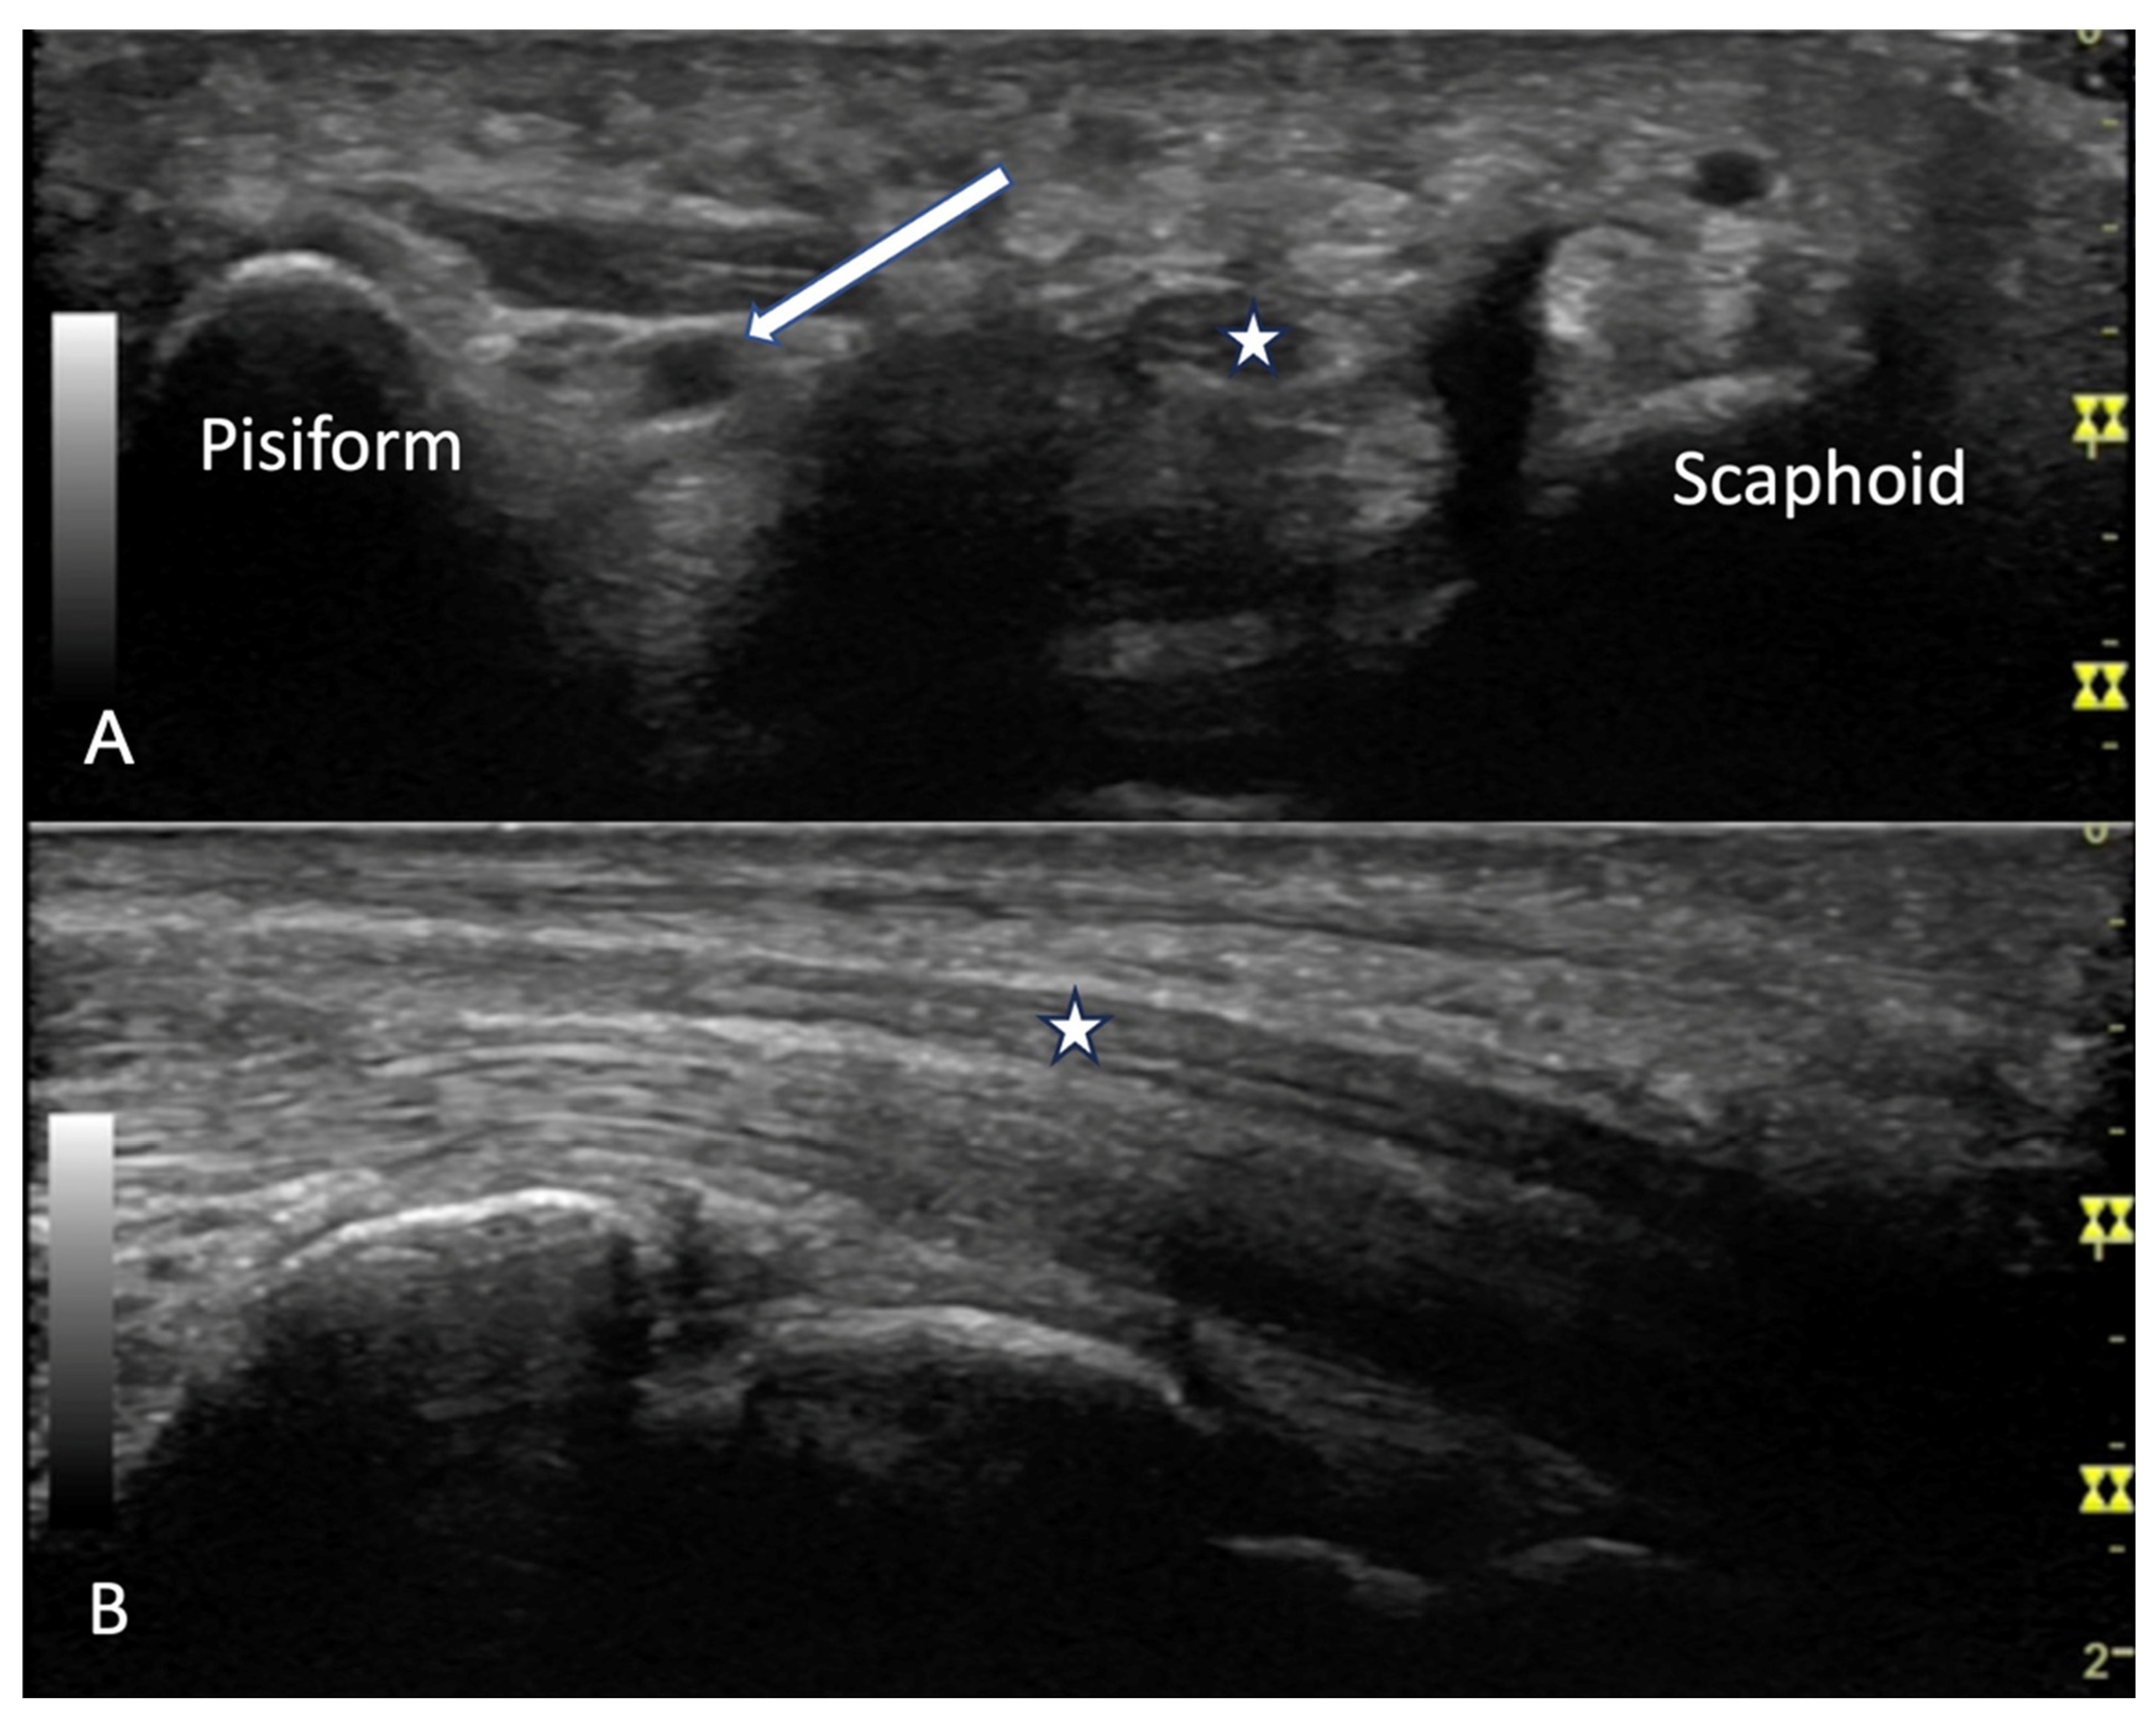

4.2. Evaluation of the Wrist

4.2.2. Volar Aspect

4.2.3. Ulnar Aspect